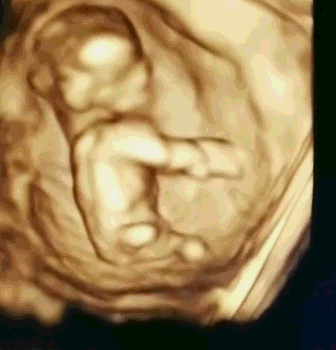

大连美琳达妇儿医院NT检查费用是多少?NT即颈项透明层,指胎儿颈后皮下组织内液体积聚的厚度,反映在超声声像图上,即为胎儿颈椎水平矢状切面上颈后皮肤至皮下软组织之间无回声层的厚度。那么,大连美琳达妇儿医院NT检查费用是多少?

美国GE高清彩超设备,该设备是目前筛查胎儿畸形的全面设备,可清楚观察胎儿的生长发育情况,完整获取临床超声诊断医学信息,为医生准确诊断提供了有力的科学依据。同时,该设备具有安全辐射小、成像更清晰、数值更精确等特点,因而其检测结果与一般医院普通彩超相比更值得信赖。

NT检查是孕早期排除胎儿异常的必查项目。为了在妊娠较早阶段诊断染色体疾病和发现多种原因造成的胎儿异常,所有孕妈咪们都应该积极地做好检查,以保证宝宝的顺利诞生。而NT检查最好在怀孕11~14周做,超过14周检查会不准确。